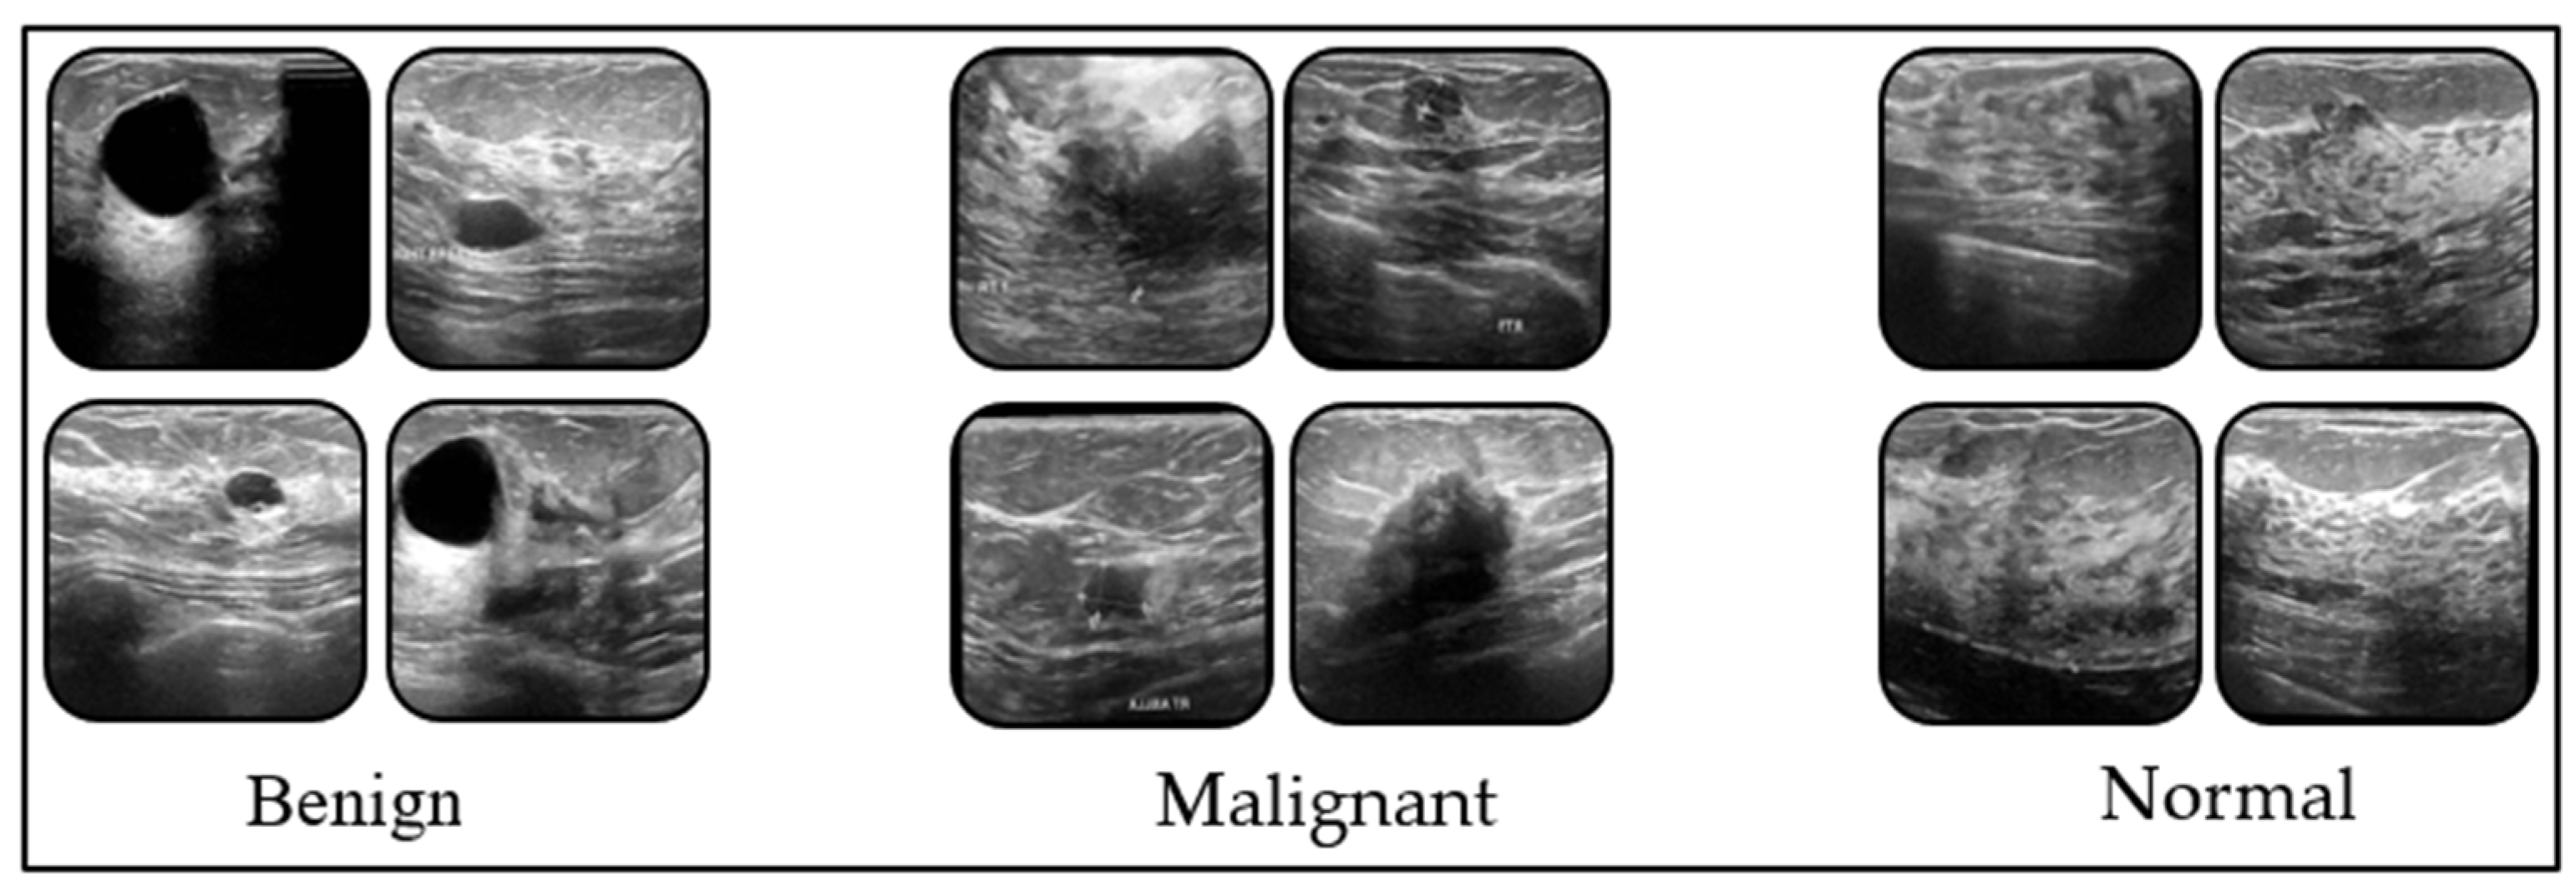

2.1. Dataset